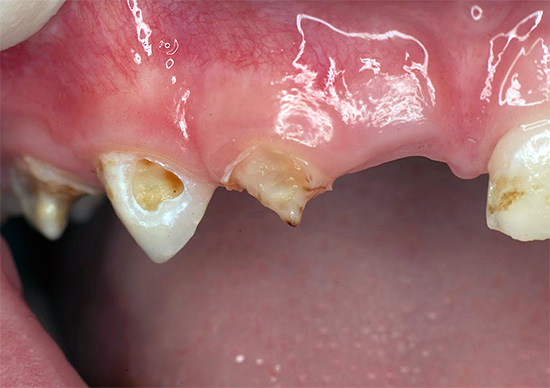

A foto mostra um dente de leite com pulpite com uma cárie profunda: